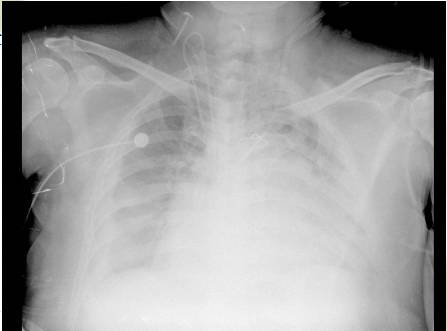

2.超滤前后胸片变化

超滤前

超滤后2日